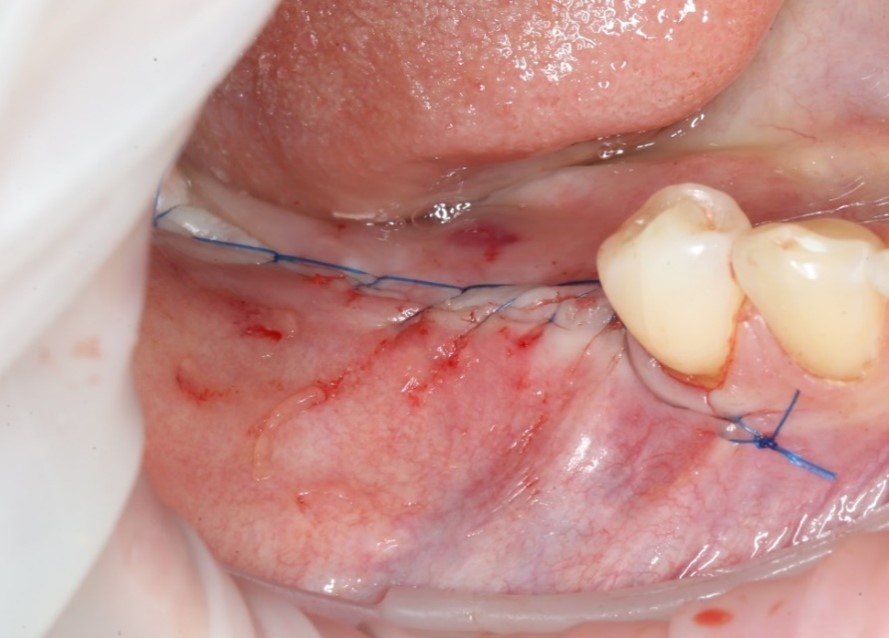

Операция закончена:

Операция, классически, заканчивается наложением швов: